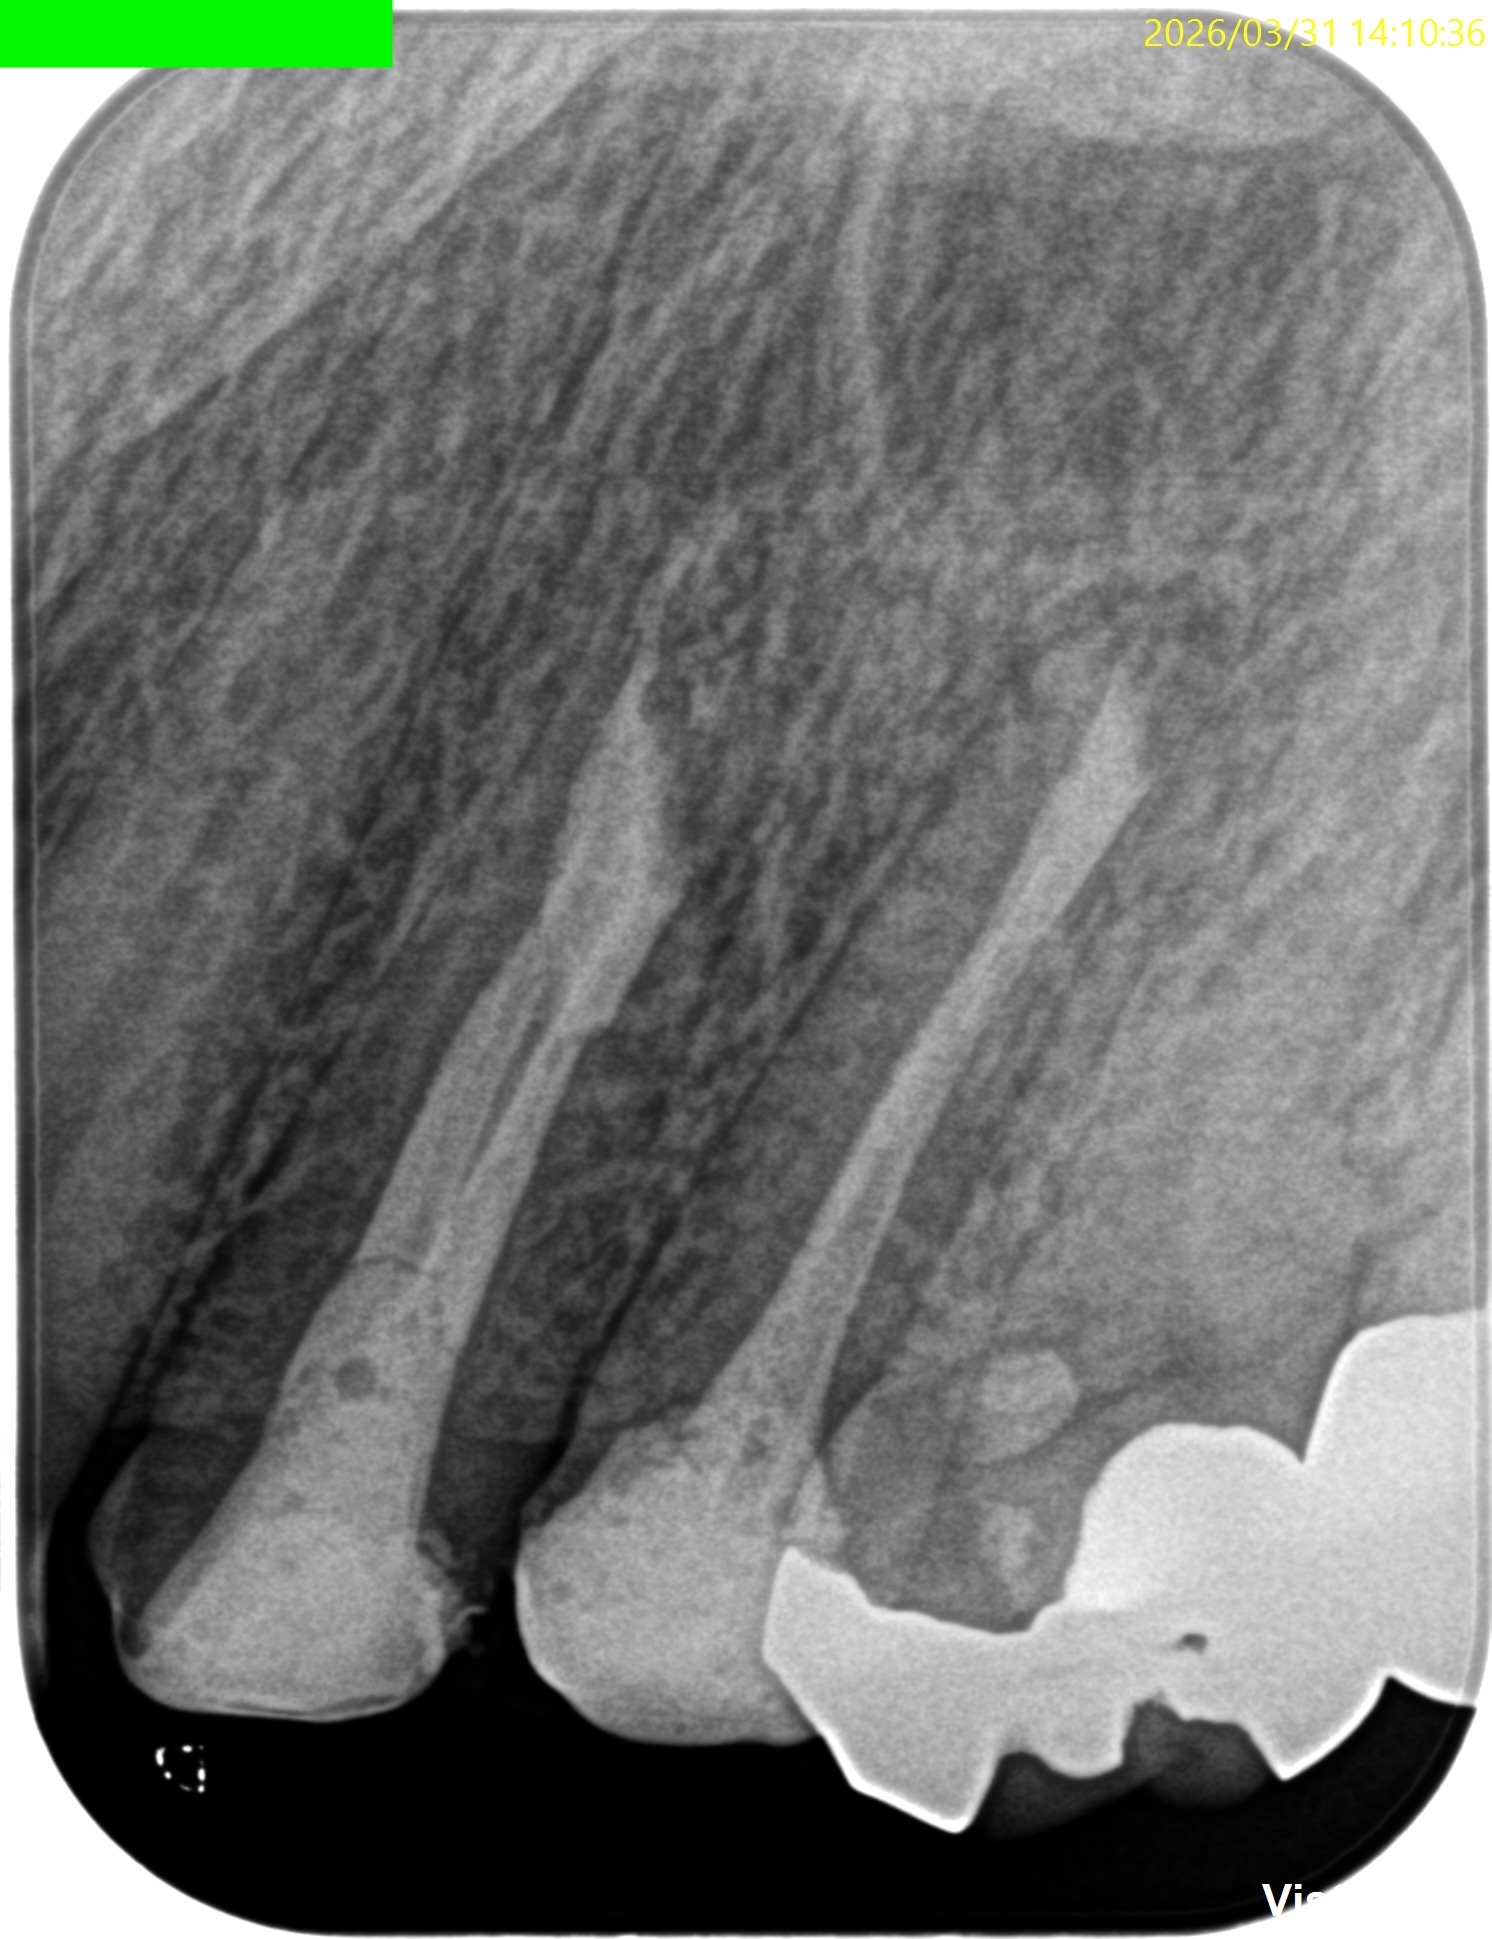

#12,13 Apicoectomy 6M recall(2026.3.31)

#13

術前・直後と比較した。

最終補綴はOKである。